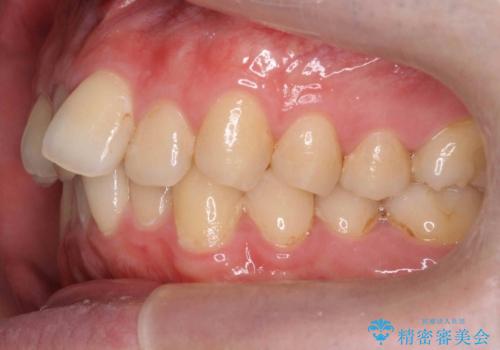

奥歯のかみ合わせを特に変えず、前歯の並びを整える治療をおこないました。

奥歯のかみ合わせは1本分ずれているとはいえ、1歯対2歯の交互のかみ合わせになっているため、そのままにしてもそこまで大きなデメリットはありません。

今回は右のかみ合わせはそのままにしました。左は特に初めから問題ない状態でした。

右のかみ合わせを変えず部分矯正にしたことによって、治療が短期間で済み、また、ワイヤーでなくインビザラインで治療が可能、歯も抜かなくて済むなどメリットの多い方法であるといえます。